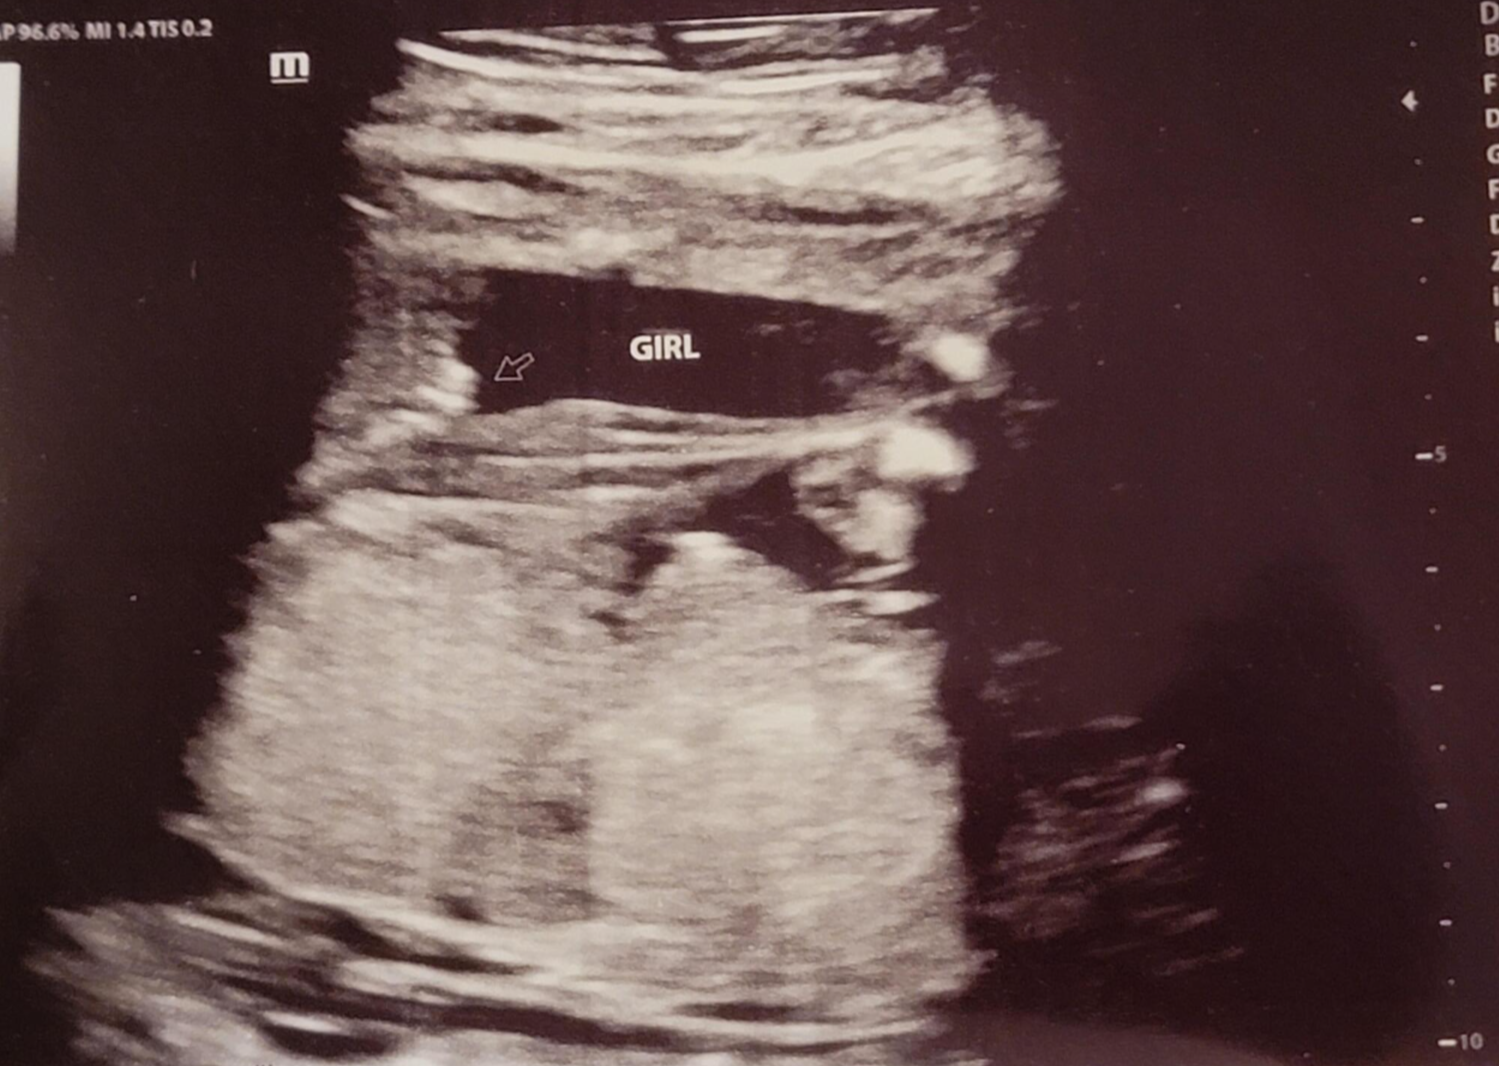

20주 정밀초음파를 받았는데 아이 건강상태를 꼼꼼하게 확인하고 마지막으로 성별을 확인했는데 딸이라고... 저에게 성별 반전이 있었어요~ 그래서 믿을 수가 없어서 제가 초음파 검사를 했을 때마다 아들이라고 했는데 지금 딸이라 해서 너무 혼란스럽다고 하니 다시 누워보라며 다시 봐주셨는데 역시나 딸 ^^~ 확실한 성별 반전! 딸을 더 원했던 남편은 저의 기분을 생각하지 않고 너무 행복해하더라고요 ㅋㅋㅋㅋㅋ ;;